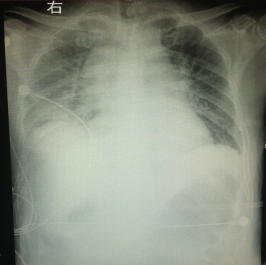

全身麻醉下宫腔镜术后急性左心衰一例

作者:黄昕, 桂平 ,张媛,伍静,华中科技大学同济医学院附属协和医院 患者,女,30岁,163cm,52.5kg,ASAⅠ级。因不规则...